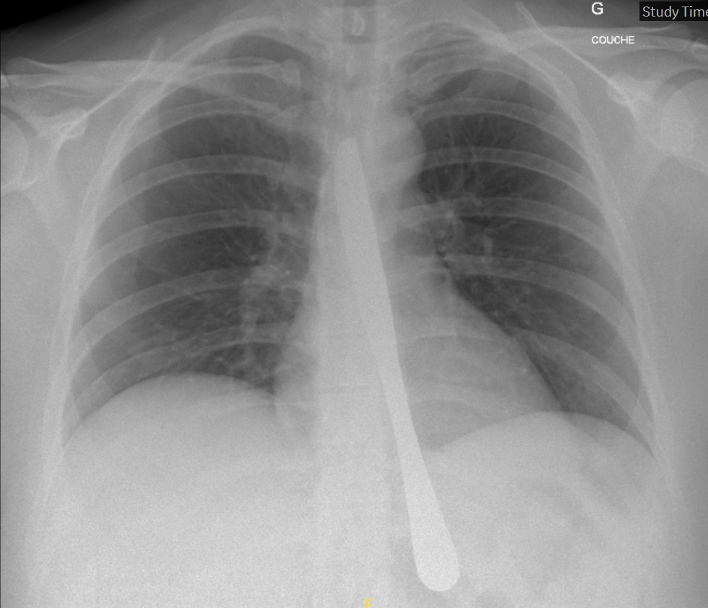

Cette radiographie est celle d’une jeune patiente se présentant aux urgences après récidive d’ingestion volontaire d’un objet métallique dans un contexte de pathologie psychiatrique.

La question qui se pose lorsque le geste est extrêmement répétitif est : peut-on éviter l’endoscopie systématique ?

Les guidelines de l’European Society of Gastrointestinal recommandent d’effectuer un CT chez toutes les personnes présentant une suspicion de perforation ou d'autres complications pouvant nécessiter une intervention chirurgicale. Elles proposent une surveillance clinique sans nécessité de retrait endoscopique pour la prise en charge des patient·es asymptomatiques ayant ingéré des objets contondants et de petite taille (à l'exception des piles plates et des aimants).

Elles recommandent une OGD thérapeutique urgente (dans les 2 - 6 heures) pour les corps étrangers provoquant une obstruction œsophagienne complète, et pour les objets pointus ou les piles dans l'œsophage ainsi que dans les 24 heures pour les autres corps étrangers œsophagiens sans obstruction complète (et suggérée pour les corps étrangers dans l'estomac tels que les objets pointus, les aimants, les piles et les objets larges/longs) et dans les 72 heures pour les corps étrangers contondants de taille moyenne dans l'estomac. En l’absence de complications la prise en charge peut-être ambulatoire.

Il n’y a pas de spécificité faite pour les patient·es qui ingèrent de façon volontaire que ce soit dans un but de recherche de soins (patient·es incarcéré·es) ou lié à une pathologie psychiatrique.